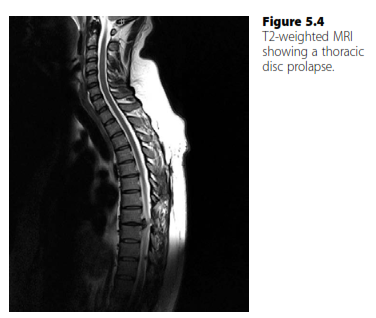

A thoracic disc prolapse (rare) will typically present with symptoms and signs of spinal cord compression associated with thoracic back pain (Figure 5.4). The discs are usually calcified and require decompression from the front. Treatment therefore is via a thoracotomy and partial vertebrectomy.